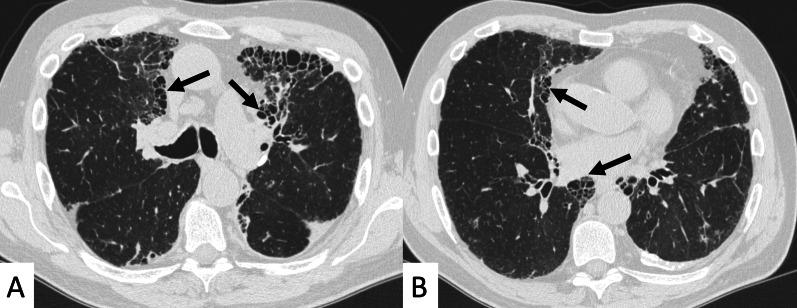

Connective tissue diseases (CTDs) include a spectrum of disorders that affect the connective tissue of the human body; they include autoimmune disorders characterized by immune-mediated chronic inflammation and the development of fibrosis. Lung involvement can be misdiagnosed, since pulmonary alterations preceded osteo-articular manifestations only in 20% of cases and they have no clear clinical findings in the early phases. All pulmonary structures may be interested: pulmonary interstitium, airways, pleura and respiratory muscles. Among these autoimmune disorders, rheumatoid arthritis (RA) is characterized by usual interstitial pneumonia (UIP), pulmonary nodules and airway disease with air-trapping, whereas non-specific interstitial pneumonia (NSIP), pulmonary hypertension and esophageal dilatation are frequently revealed in systemic sclerosis (SSc). NSIP and organizing pneumonia (OP) may be found in patients having polymyositis (PM) and dermatomyositis (DM); in some cases, perilobular consolidations and reverse halo-sign areas may be observed. Systemic lupus erythematosus (SLE) is characterized by serositis, acute lupus pneumonitis and alveolar hemorrhage. In the Sjögren syndrome (SS), the most frequent pattern encountered on HRCT images is represented by NSIP; UIP and lymphocytic interstitial pneumonia (LIP) are reported with a lower frequency. Finally, fibrotic NSIP may be the interstitial disease observed in patients having mixed connective tissue diseases (MCTD). This pictorial review therefore aims to provide clinical features and imaging findings associated with autoimmune CTDs, in order to help radiologists, pneumologists and rheumatologists in their diagnoses and management.

结缔组织病(CTDs)包括一系列影响人体结缔组织的疾病;它们包括以免疫介导的慢性炎症和纤维化发展为特征的自身免疫性疾病。肺部受累可能会被误诊,因为肺部改变仅在20%的病例中先于骨关节炎表现出现,且在早期阶段没有明确的临床发现。所有肺部结构都可能受累:肺间质、气道、胸膜和呼吸肌。在这些自身免疫性疾病中,类风湿关节炎(RA)的特征是普通型间质性肺炎(UIP)、肺结节和伴有空气潴留的气道疾病,而系统性硬化症(SSc)常表现为非特异性间质性肺炎(NSIP)、肺动脉高压和食管扩张。NSIP和机化性肺炎(OP)可见于多发性肌炎(PM)和皮肌炎(DM)患者;在某些情况下,可观察到小叶周围实变和反晕征区域。系统性红斑狼疮(SLE)的特征是浆膜炎、急性狼疮性肺炎和肺泡出血。在干燥综合征(SS)中,HRCT图像上最常见的表现是NSIP;UIP和淋巴细胞间质性肺炎(LIP)的报道频率较低。最后,纤维化NSIP可能是混合性结缔组织病(MCTD)患者中观察到的间质性疾病。因此,本图像综述旨在提供与自身免疫性CTDs相关的临床特征和影像学表现,以帮助放射科医生、呼吸科医生和风湿病科医生进行诊断和管理。